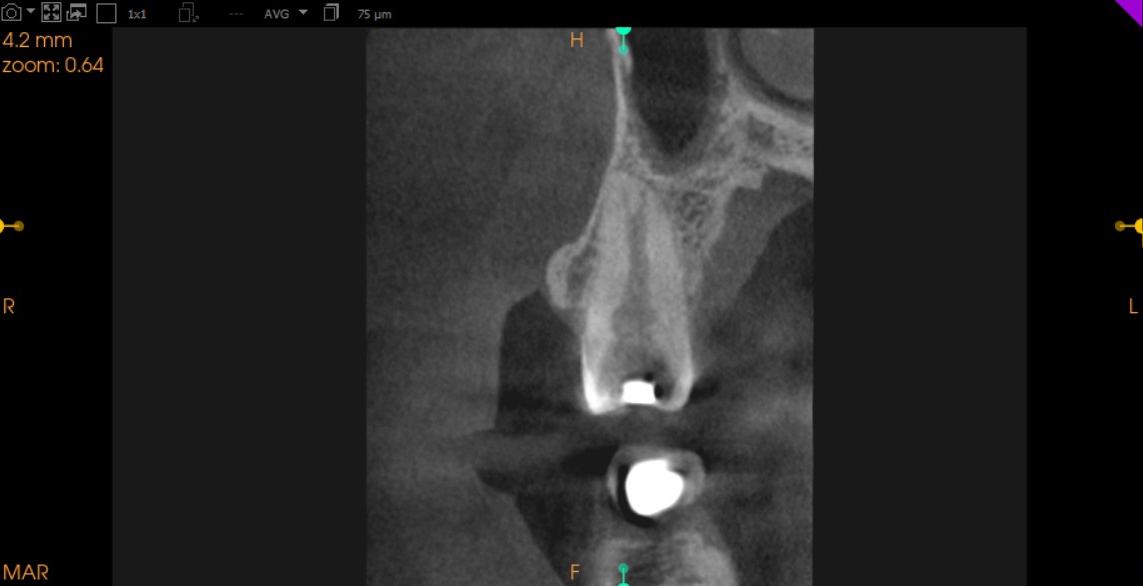

Pre-Op Root Canal